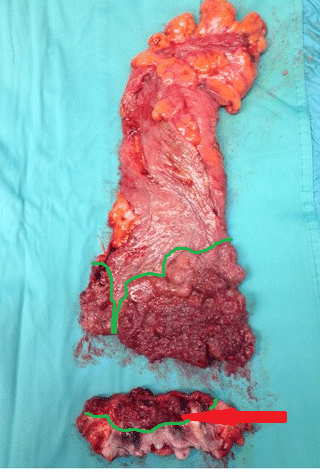

Παρασκεύασμα κοιλιοπερινεϊκής εκτομής ορθού. Διακρίνεται σχεδόν πλήρης κατάληψη του αυλού του ορθού, εκτεινόμενη έως την ορθοπρωκτική συμβολή, με συνοδό διήθηση των σφιγκτήρων (Ευγενική παραχώρηση Dr. V. Penopoulos)